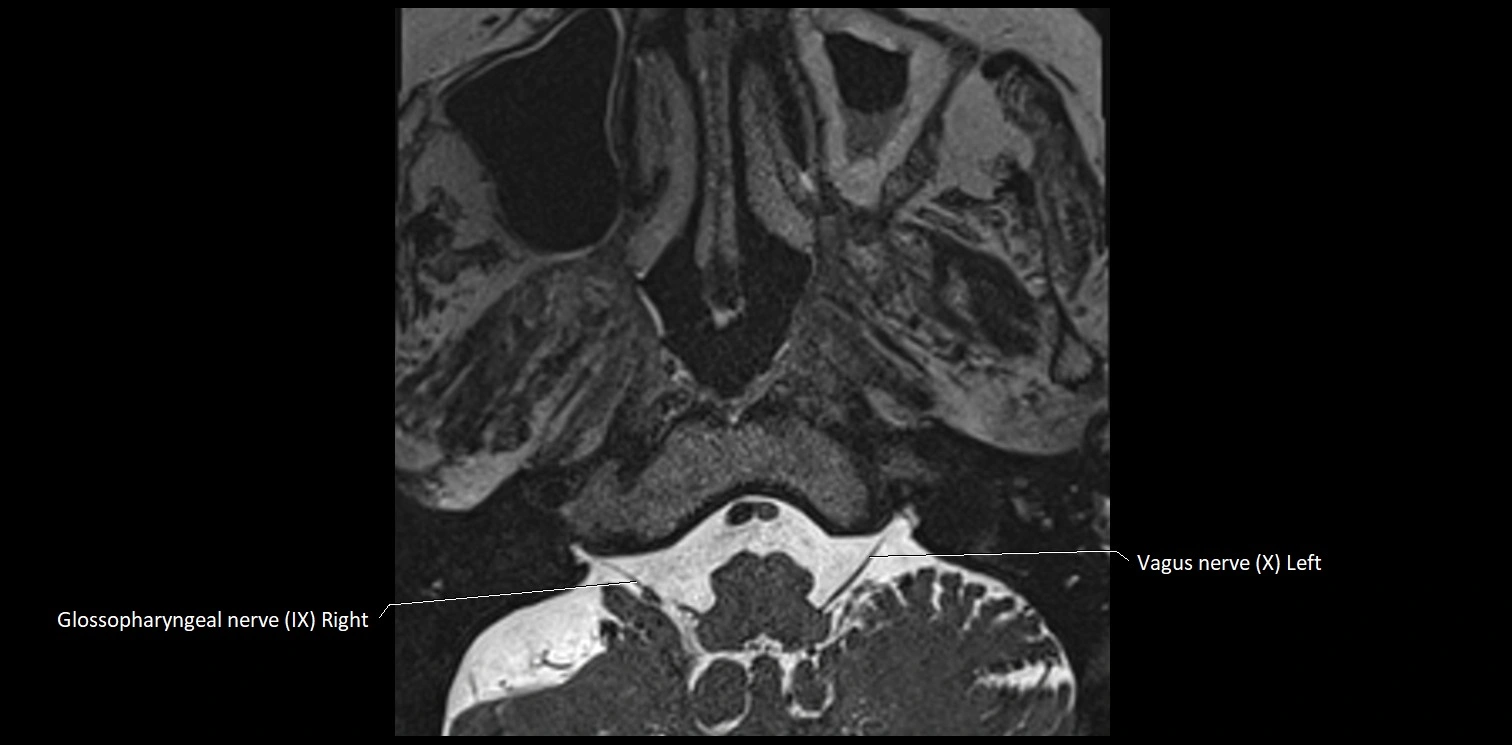

MRI Appearance

• The abducens nerve is a small, thin, linear structure

• Best visualized on high-resolution T2-weighted 3D MRI sequences (e.g., FIESTA or CISS)

• Seen as a hypointense (dark) line running from the brainstem at the pontomedullary junction, traversing the prepontine cistern, and entering Dorello’s canal under the petrosphenoidal ligament, then into the cavernous sinus, and finally the orbit

• May be challenging to visualize in standard MRI due to its small size

• Pathology may be inferred by absence, displacement, or enhancement of the nerve

MRI images

image